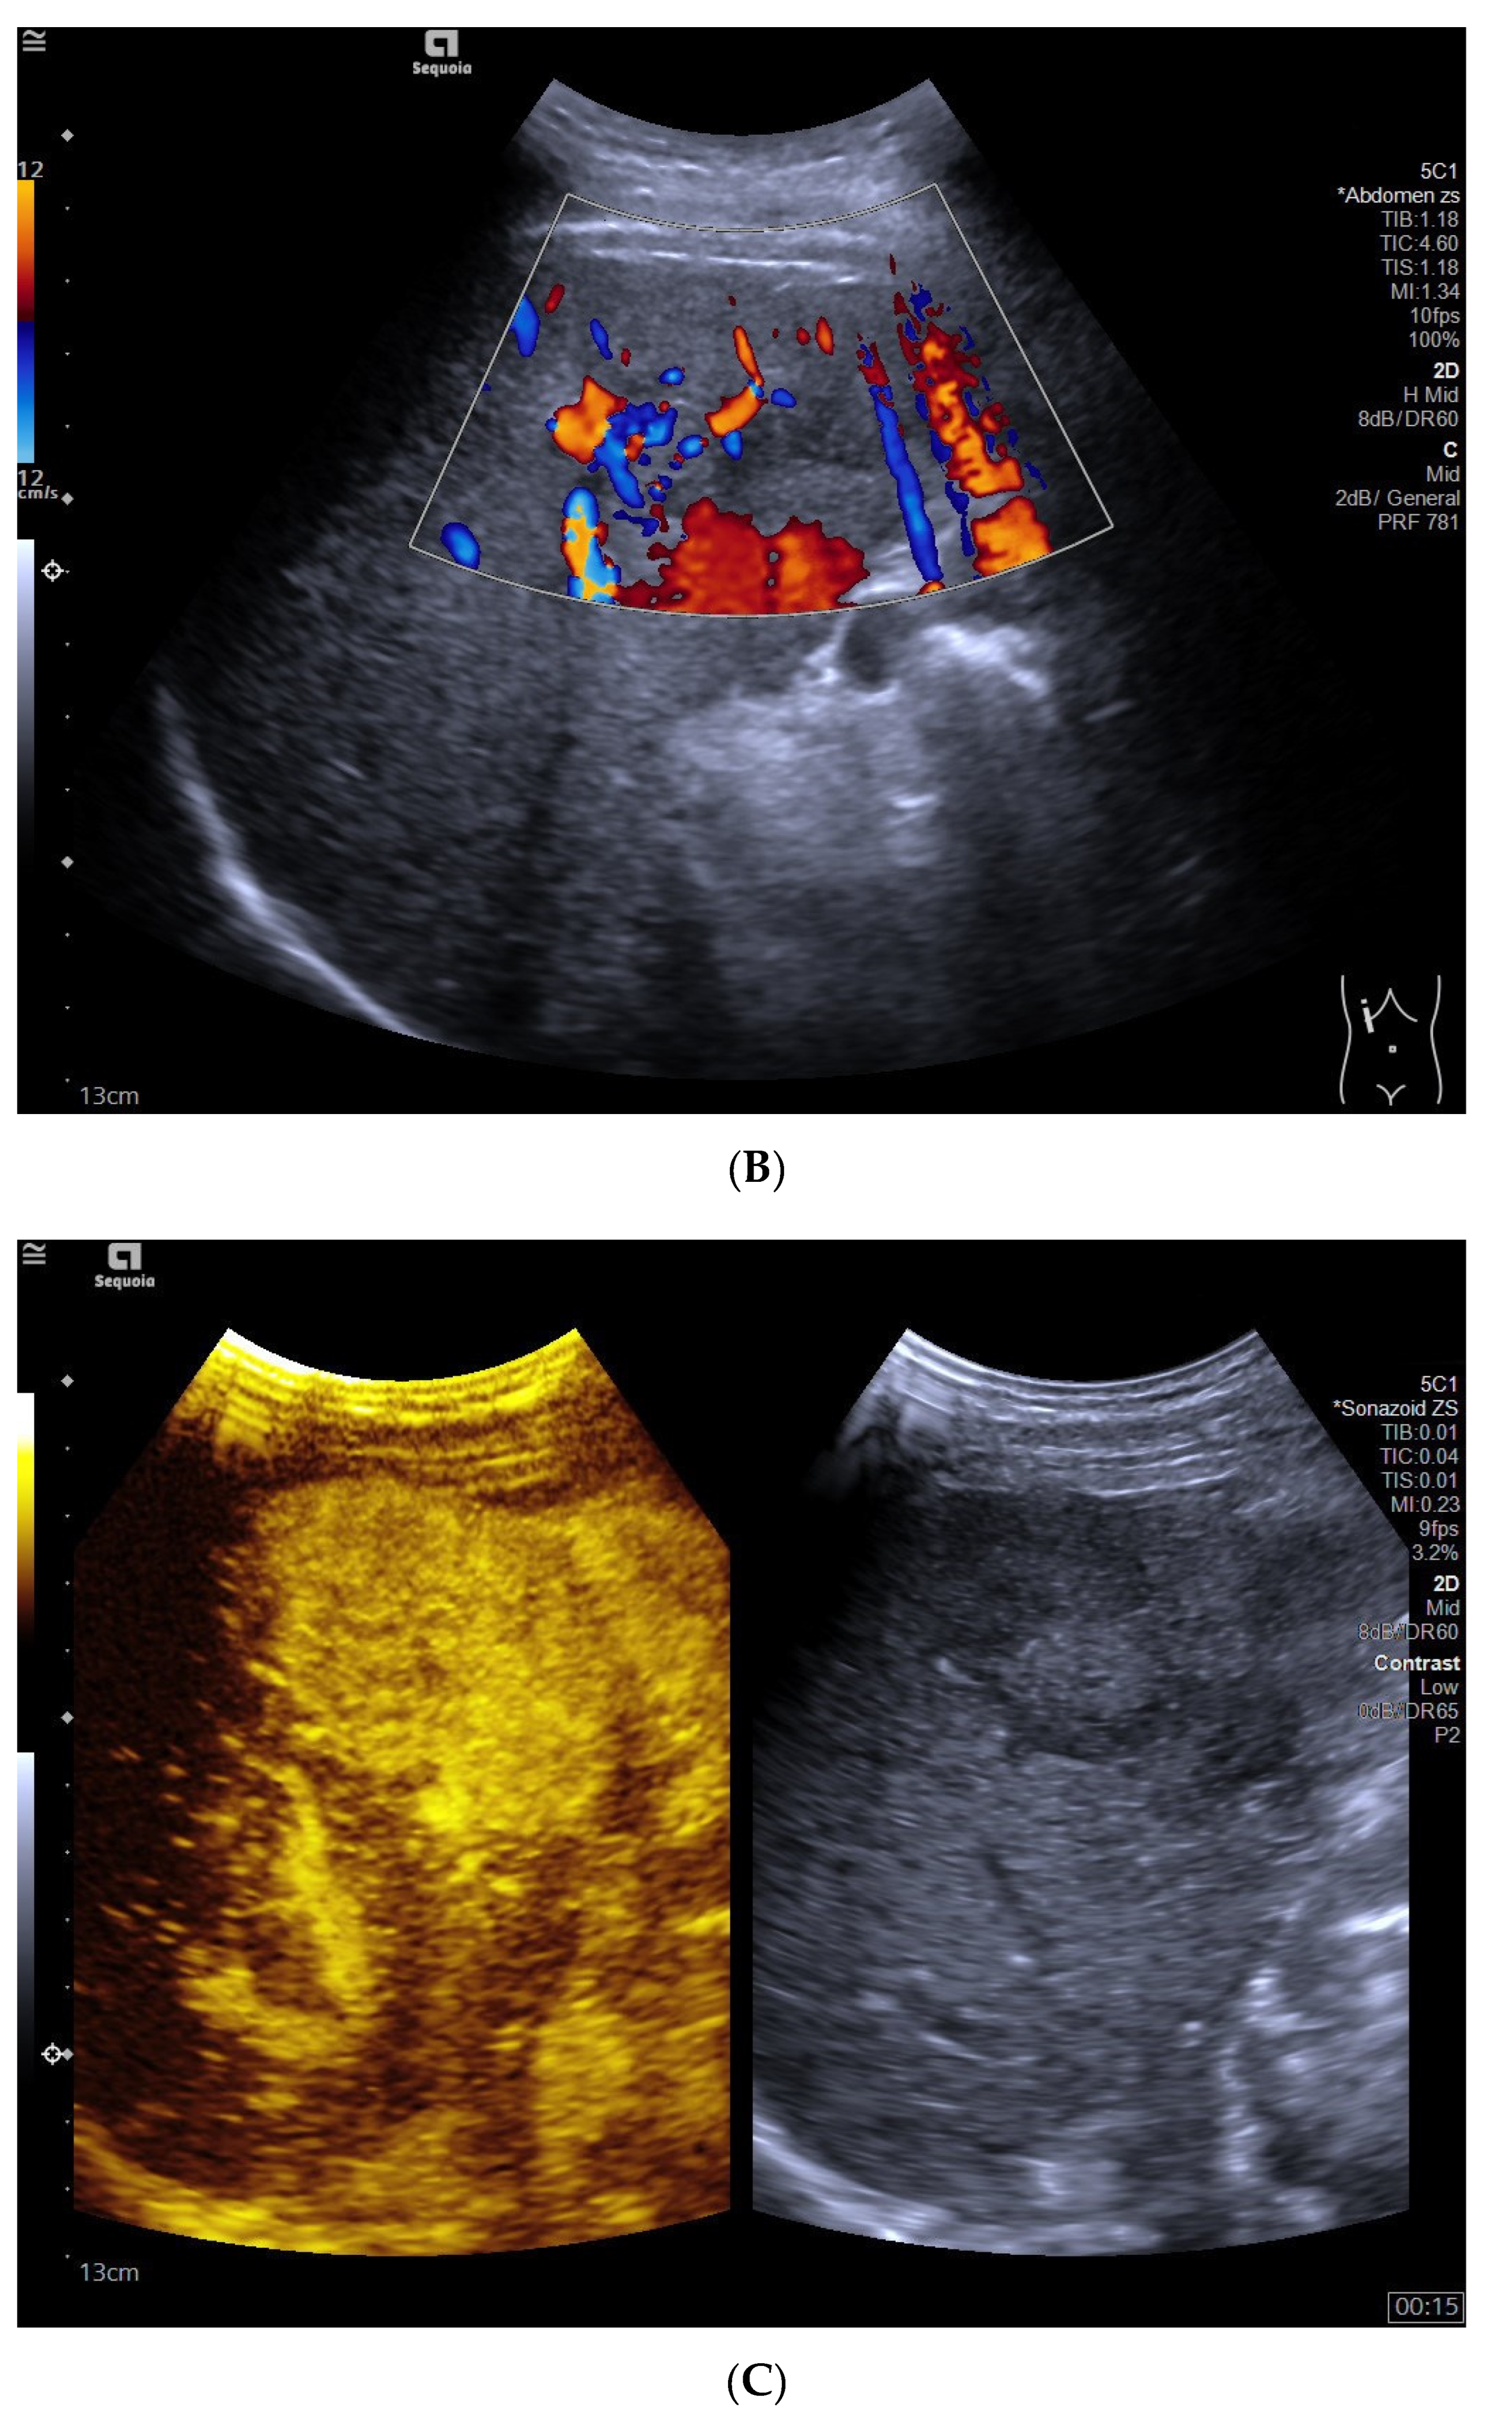

3.4. CEUS Features

3.5. Time Begin to Washout